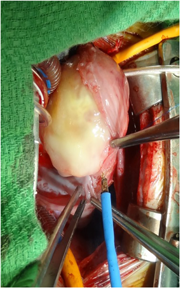

多量の心嚢液貯留があり,心タンポナーデへの進行が危惧されたため,緊急で腫瘍摘出術を施行した.

心膜切開により淡黄色透明で漿液性の心嚢水が確認された.右房内腫瘍の範囲は洞結節付近から三尖弁輪まで及び,右冠動脈とも接していた.洞結節と腫瘍の辺縁の間で右房壁を切開し,洞結節,三尖弁輪,右室心筋と腫瘍の間を剥離し,腫瘍を摘出した.腫瘍は全切除できたと判断した(Fig. 3).

Pediatric Cardiology and Cardiac Surgery 32(4): 314-318 (2016)

Fig. 3 Intraoperative view of the cardiac mass with a white, glistening surface